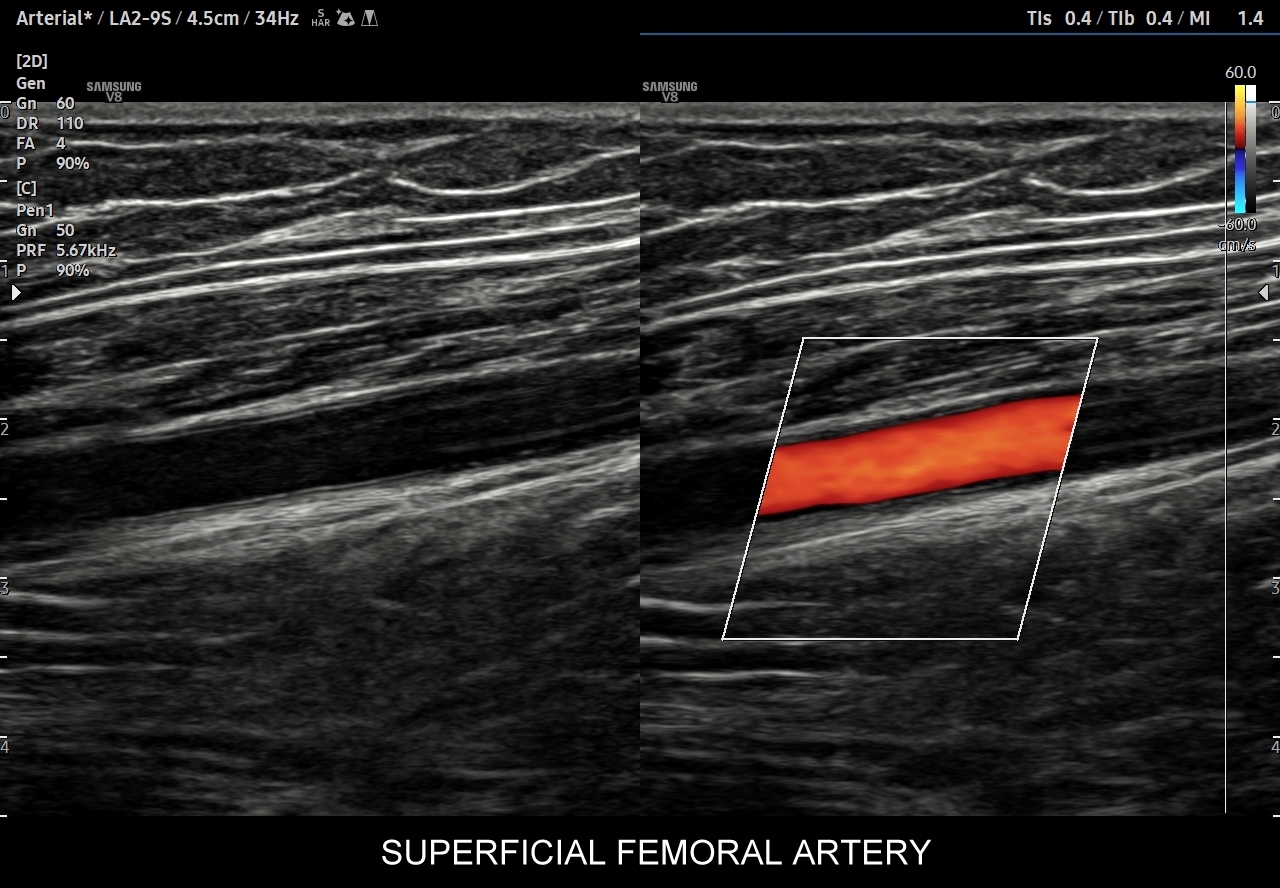

- Z kolei profile o wysokiej pulsacyjności charakteryzują się tym, iż posiadają wąskie i ostre piki skurczowe, a w fazie rozkurczowej odwrócone lub/i nieobecne przepływy. Profile tego typu występują w tętnicach unaczyniających kończyny.

W przypadku tętnic podążających do kończyn w warunkach spoczynkowych obserwuje się charakterystyczne wielozałamkowe profile przepływów zawierające od 2 do nawet 4 następujących po sobie przeciwstawnych załamków o zmniejszającej się amplitudzie, przy czym w tętnicach tych zwykle nie obserwuje się ciągłego przepływu w fazie rozkurczowej. Stały lub prawie stały przepływ rozkurczowy, tj. przepływ o pośredniej pulsacyjności, może pojawić się w tętnicach kończyn w trakcie intensywnego wysiłku fizycznego.